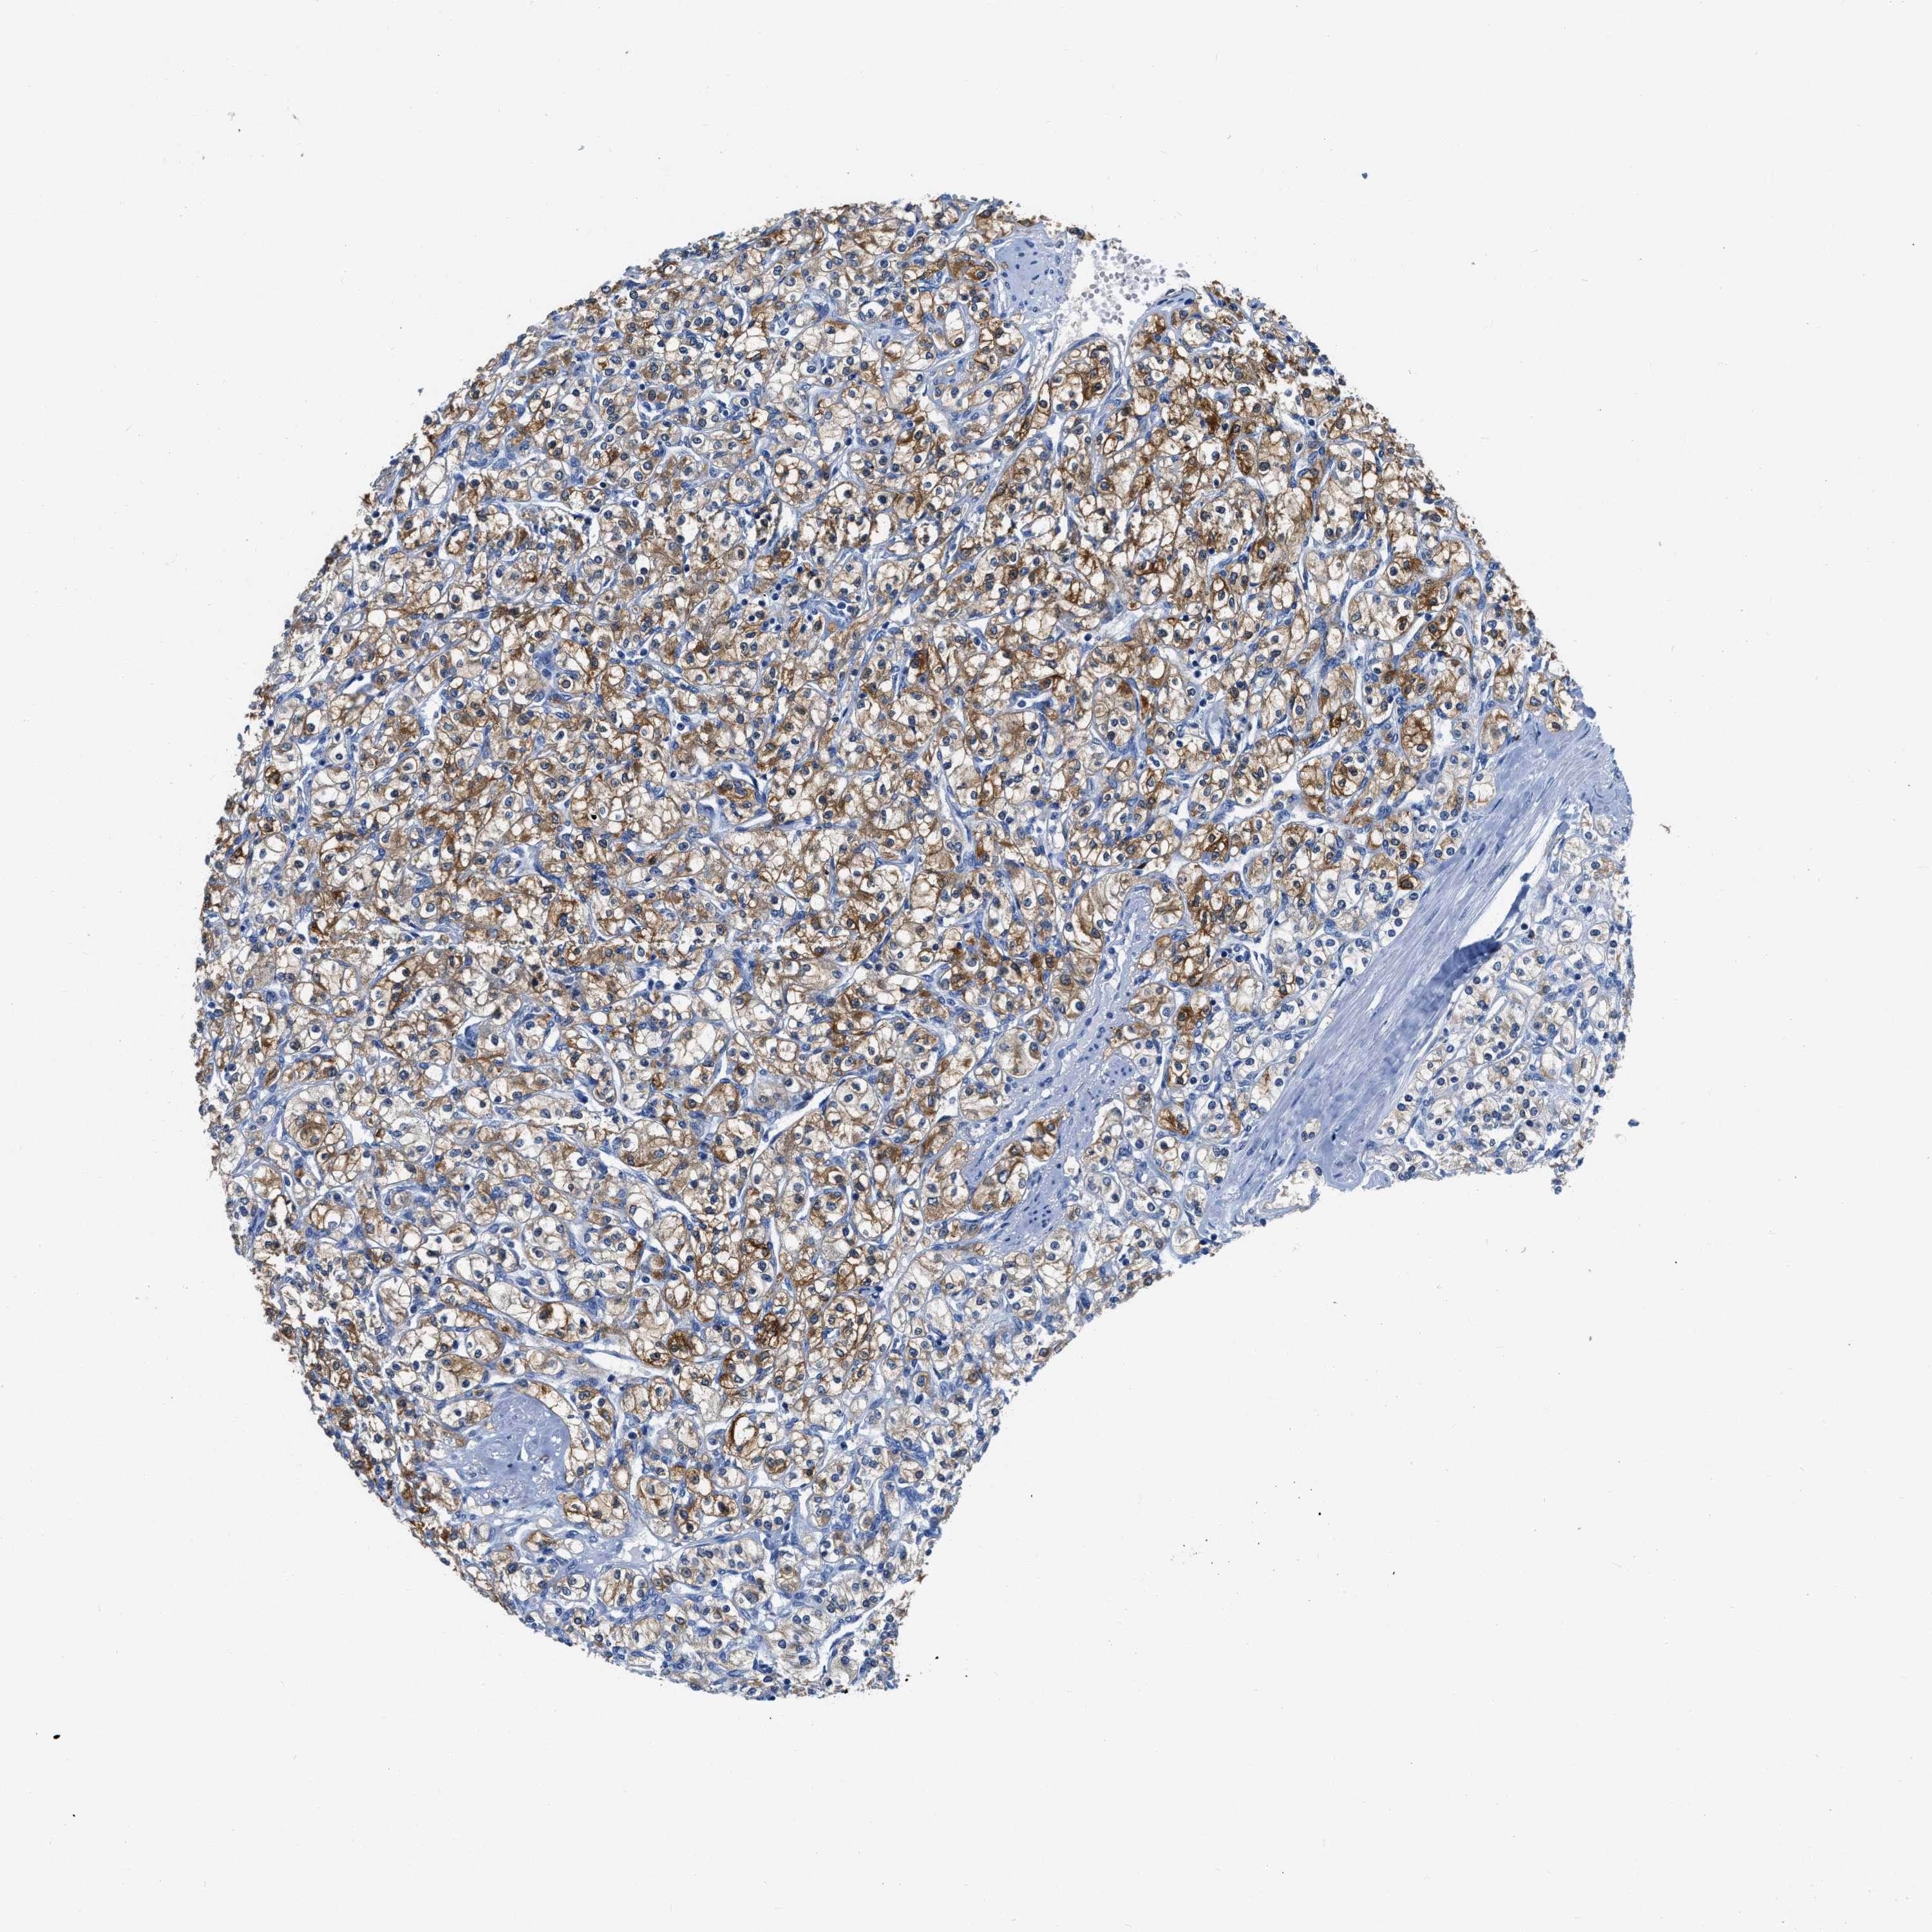

KIDNEY RENAL CLEAR CELL CARCINOMA (TCGA) - Interactive survival scatter ploti

ZDHHC13 is potential prognostic, high expression is favorable in Kidney Renal Clear Cell Carcinoma (TCGA)

: 7.91

Average pTPM 11.0

Number of samples 521